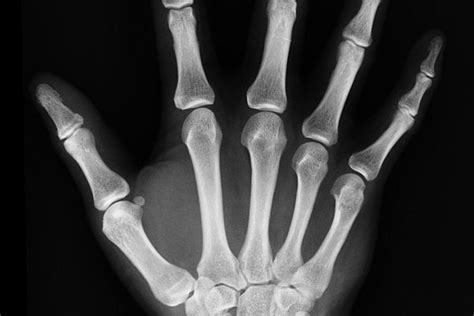

Pred operačným výkonom, ako je totálna endoprotéza bedra, je nevyhnutná dôkladná predoperačná príprava. Tá zahŕňa krvné testy, röntgenové vyšetrenie a konzultáciu s chirurgom. V deň operácie je dôležité dodržiavať pokyny lekára týkajúce sa stravy a užívania liekov.

Operácia totálnej endoprotézy bedra, ako aj iné operácie s implantáciou umelého kĺbu, zvyčajne trvá niekoľko hodín. Počas zákroku chirurg odstraňuje poškodené časti kĺbu (chrupavku a kosť) a nahrádza ich umelými materiálmi, ktoré môžu byť vyrobené z kovov, plastov alebo keramiky.